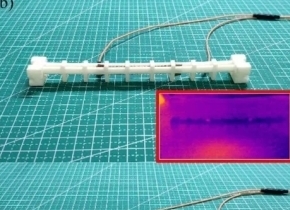

挑战在于有效地提高亚细胞水平的图像分辨率,因为光扰乱不可避免地会丢失信息。在AIP Publishing出版的APL Photonics中,荷兰的研究人员通过基于散斑的压缩成像(SBCI)解决了这一挑战,该技术利用了多模光纤的光扰频优势。

SBCI改变激光束的进入位置,在光纤输出端产生多个不相关的随机散斑图案。计算机算法可以根据图案及其收集的信息重建对象的图像。

与传统内窥镜和显微镜中使用的黄金标准光栅成像相比,这种“压缩成像”减少了重建质量相似或更好的图像所需的像素测量量。SBCI生成高分辨率图像的速度比传统的光栅扫描方法快11倍,空间是传统光栅扫描方法的3倍。